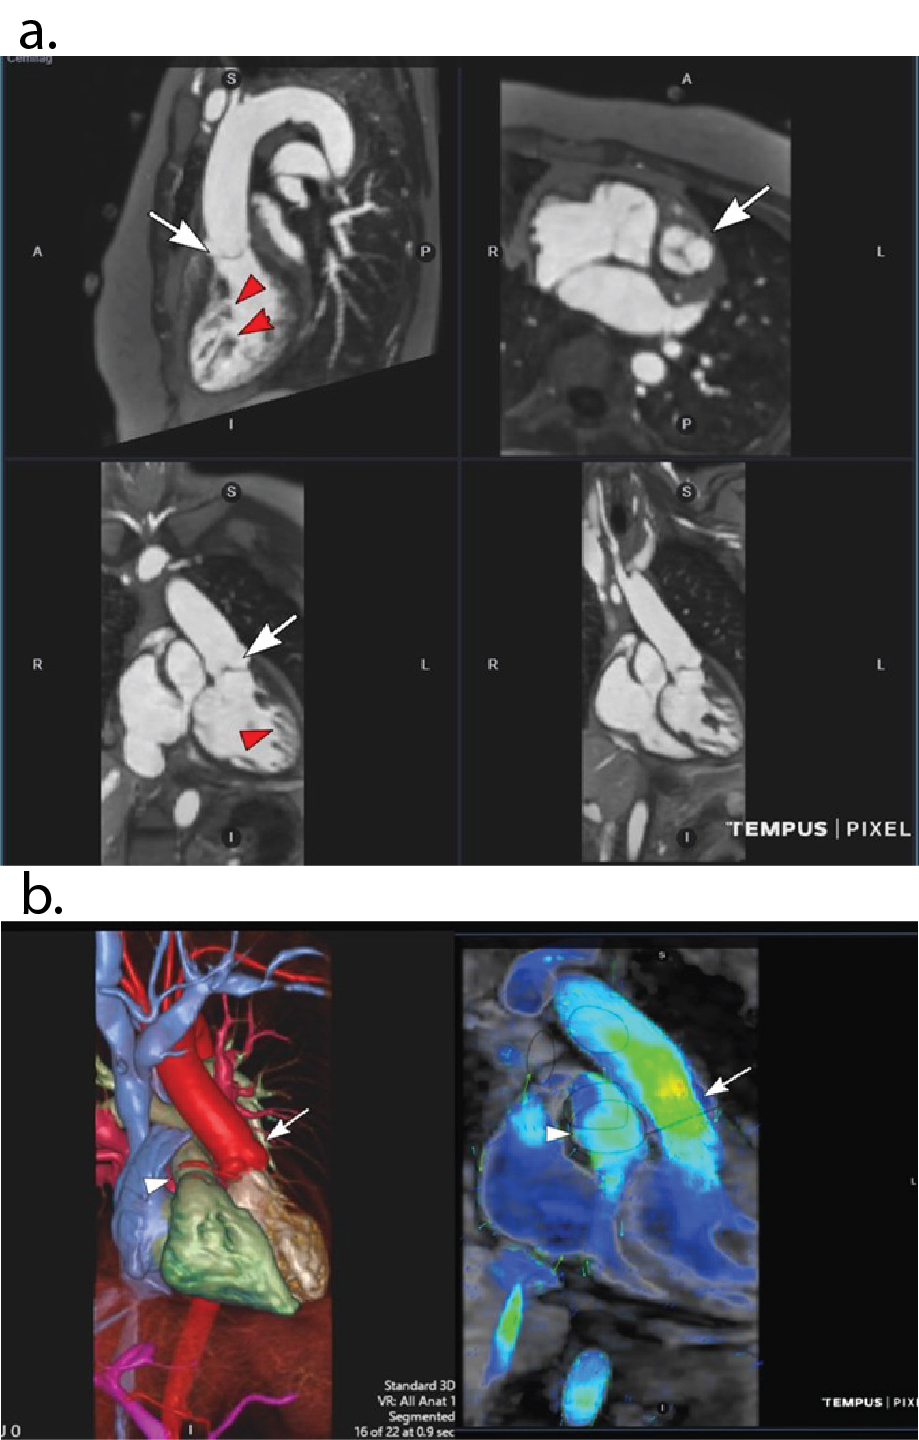

Figure 2: 42 y.o. female with mild aortic coarctation. a) Multiplanar reconstructions on OsiriX software displays one of 10 phases from BH 4D MUSIC at 3.0T . Breath-hold duration 22 secs with acceleration factor X15. Note the uniform blood signal and clear definition of the coarctation (white arrow) and left coronary artery (red arrow). b) Same patient and same acquisition as in Fig 4a. Color volume rendered frame from BH 4D MUSIC (left panel; Vitrea workstation) and corresponding 4D flow (right panel; Tempus cloud) on one of 10 phases shows the anatomy and flow field of the coarctation (arrow). c) Same patient as in Figs 2a,b. Separate BH 4D MUSIC acquisition with higher temporal resolution for full coverage cine imaging. Breath-hold duration 19 secs with acceleration factor X15. Top panel shows single phase from 2D cine at several short axis positions. Bottom panel shows corresponding short axis cine 18 phase reconstructions from BH 4D MUSIC with 3mm contiguous slices and 50 ms temporal resolution.